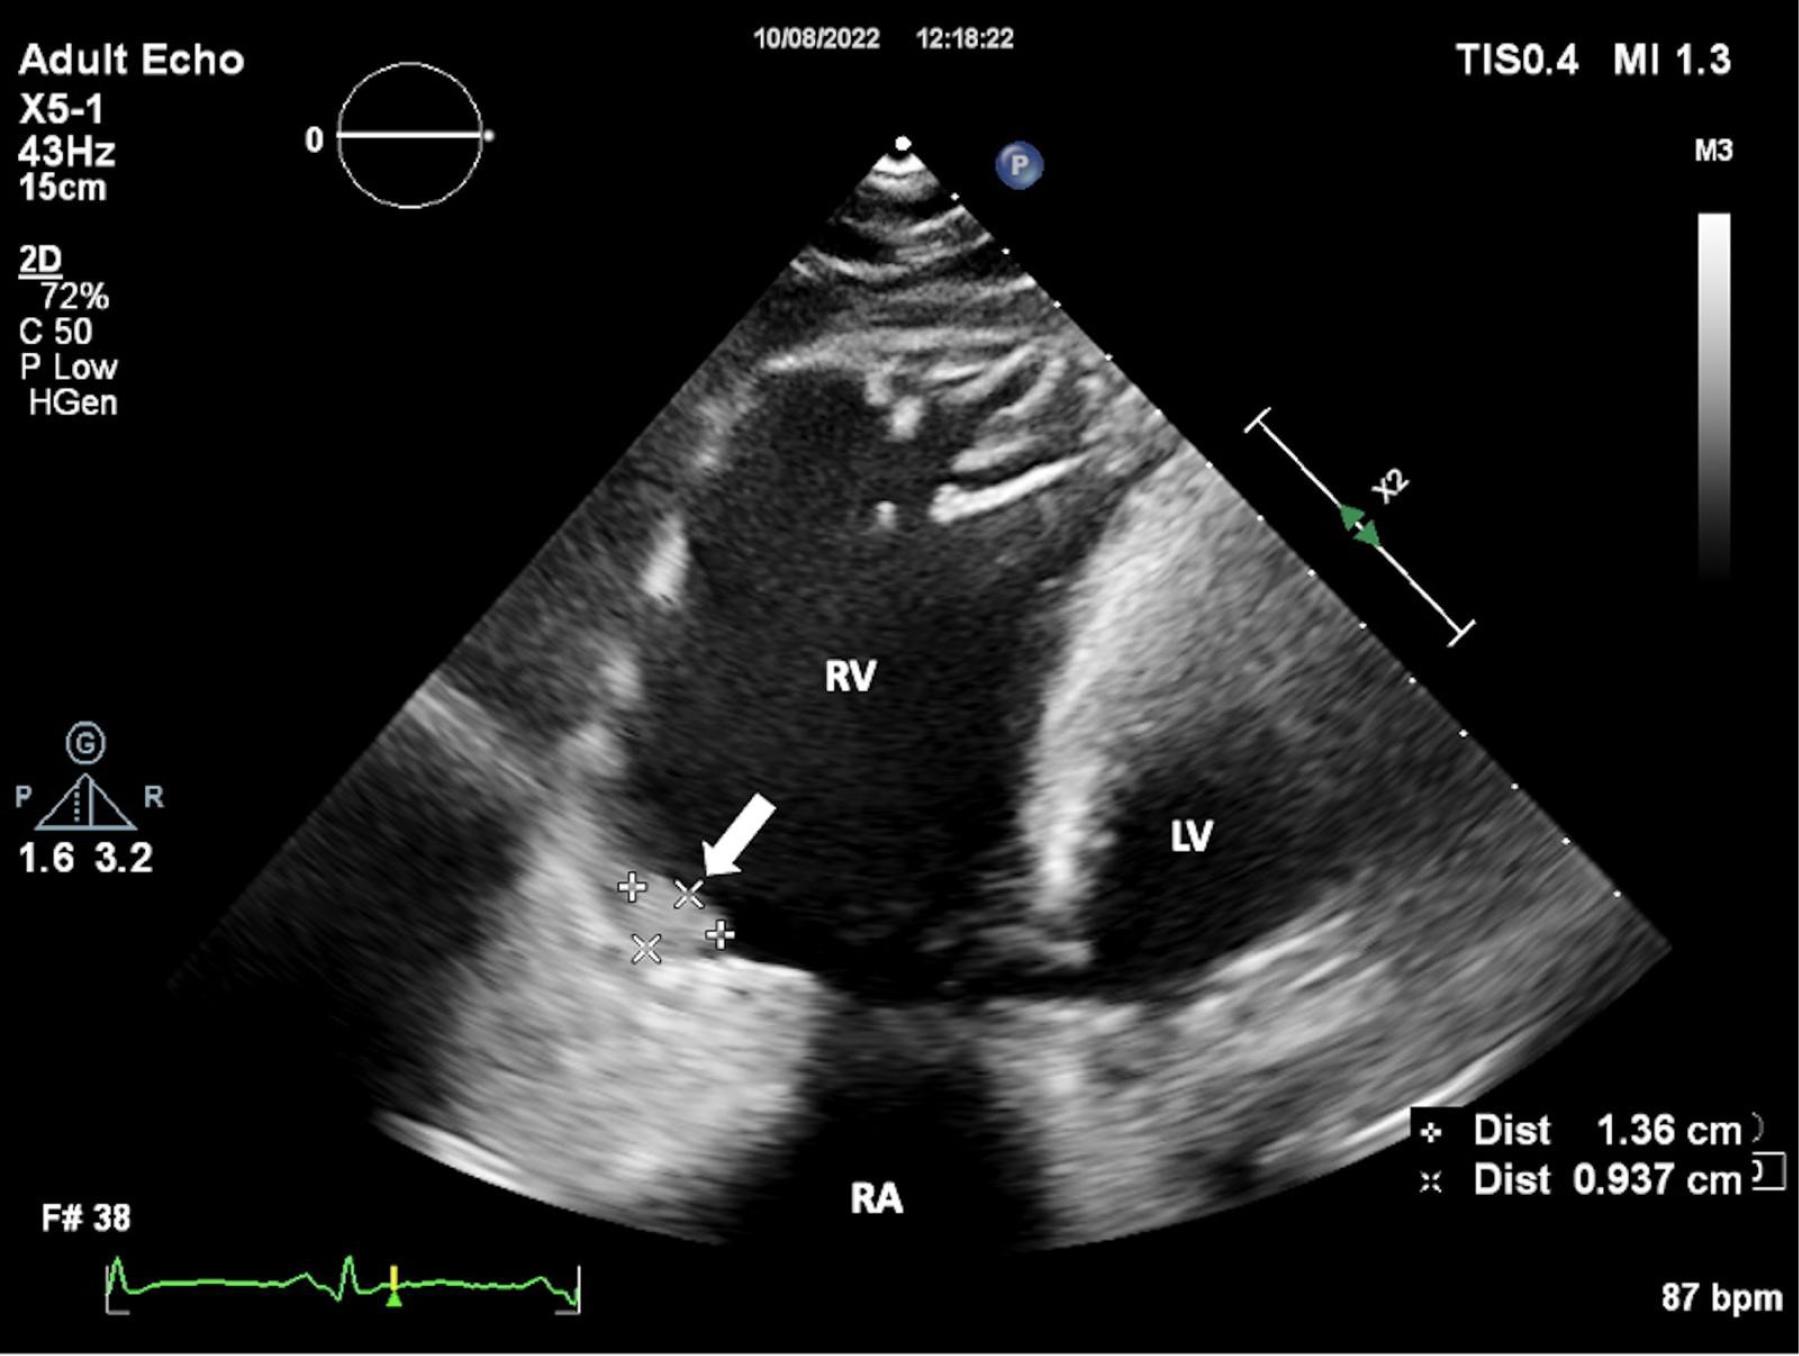

Figure 2.

Wall Irregularity of the Right Ventricle. Transthoracic echocardiography (TTE) shows the wall irregularity of the right ventricle. FIGUR LEGEND: TTE: Transthoracic Echocardiography, RA: Right Atrium, RV: Right Ventricle, LV: Left Ventricle.

A 24-year-old female patient was admitted to our tertiary center with chest pain. She had no family history of cardiac disease or sudden cardiac death. Her electrocardiogram (ECG) was sinus rhythm and T wave negativity was detected in leads V1-5. (Figure 1) TTE showed a slight decrease in LV ejection fraction as 45%, prominently dilated right heart chambers, decreased RV functions (TAPSE: 11, tricuspid annular peak systolic velocity: 7.7), severe tricuspid regurgitation (Supplementary file 1, Video 1). Additionally, an image of 13.6 x 9.3 mm, hyperechoic, consistent with thrombus was observed in the lateral wall of the RV (Figure 2). No thromboembolism was reported in the pulmonary CTA. The patient underwent cardiac magnetic resonance imaging (CMR) for morphological and functional assessment of the heart. The CMR images showed enlarged RV and right atrium, severe hypokinesia of the RV, dyskinesia in the free wall of RV and paradoxical movement in interventricular septum, and wall irregularity in both ventricles (Figure 3). In the cardiac MRI, The LV ejection fraction was 49%, the LV end-systolic volume was 143 mL, end-diastolic volume was 73 mL, and stroke output was 60 mL. The LV end-diastolic volume index (LVEDVI) was 74 mL/m2, the LV end-systolic volume index (LVESVI) was 42 mL/m2. The RV ejection fraction was 20%, the RV end-systolic volume was 430 mL, end-diastolic volume was 343 mL, and stroke output was 87 mL. The RV end-diastolic volume index (RVEDVI) was 221 mL/m2, the RV end-systolic volume index (RVESVI) was 176 mL/m2. The late gadolinium images depicted diffuse enhancement in the right ventricular free wall and inferior wall. The left ventricular inferior septum showed midwall enhancement. A nodular mass was noted on the lateral wall of RV in the vicinity of the tricuspid valve which did not uptake gadolinium and was compatible with thrombus (Figure 4). As a result of these findings, genetic analysis was performed with a high suspicion of arrhythmogenic cardiomyopathy. The genetic analysis revealed a homozygous nonsense mutation in the desmoglein-2 gene, proven to be pathogenic in databases, and the diagnosis of arrhythmogenic cardiomyopathy was definitively confirmed with the findings from TTE, ECG, CMR, and genetic tests, which are part of the aforementioned Padua criteria.